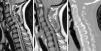

Las técnicas de imagen proporcionan una imagen anatómica excelente de la columna cervical. La elección de cada una de ellas dependerá del escenario clínico y de las alternativas terapéuticas. La radiografía simple sigue siendo fundamental, ya que permite valorar la alineación, las alteraciones óseas y el seguimiento tras el tratamiento. La mayor resolución de contraste de la resonancia magnética permite la valoración de las partes blandas, incluyendo los discos intervertebrales, los ligamentos, la médula ósea y la médula espinal. El papel de la tomografía computarizada en el estudio de la patología degenerativa ha cambiado en los últimos tiempos debido a la gran resolución espacial y su capacidad para visualizar el componente óseo.

Imaging techniques provide excellent anatomical images of the cervical spine. The choice to use one technique or another will depend on the clinical scenario and on the treatment options. Plain-film X-rays continue to be fundamental, because they make it possible to evaluate the alignment and bone changes; they are also useful for follow-up after treatment. The better contrast resolution provided by magnetic resonance imaging makes it possible to evaluate the soft tissues, including the intervertebral discs, ligaments, bone marrow, and spinal cord. The role of computed tomography in the study of degenerative disease has changed in recent years owing to its great spatial resolution and its capacity to depict osseous components.